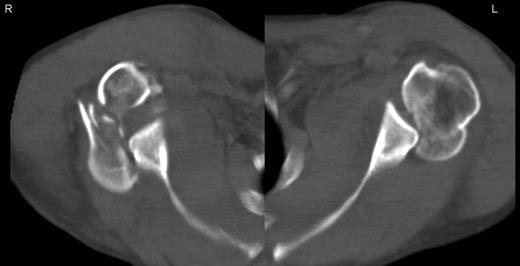

A 48-year-old patient was referred to a level I trauma center after the first incidence of an epileptic convulsion. The patient was alert and oriented with retrograde amnesia from the time of convulsion. Peripheral neurology was normal. The X-rays showed bilateral posterior shoulder dislocation with fractures of both humeral heads (Fig. 1). A CT of the head and both shoulders was performed to exclude intracerebral pathology and to achieve better demonstration of the shoulder fractures (Fig. 2). According to the AO fracture classification, he had a 11-C3.1 fracture on the left side and a 11-C3.3 fracture on the right side. The right side fracture was treated with a cementless hemiarthroplasty (OrTra®, Zimmer, Germany), while an open reduction and internal fixation (ORIF) with an angular stable plate (Philos®, Synthes, Germany) was performed on the left. Despite the high incidence for humeral head necrosis after ORIF in this fracture type, this option was chosen based on the young age of the patient. Postoperative X-rays and CT showed adequate positions of the implants (Fig. 3). The shoulders were immobilized in Gilchrist bandages followed by passive mobilization for the first 6 weeks by physiotherapy with a limitation for abduction and anteversion to 90°. There were no complications intraoperatively or in the first postoperative time. Patient was discharged after 8 days. Antiepileptic therapy was initiated with 5 mg clobazam and subsequent increasing doses over the following weeks. There were no more signs of epilepsy in the follow-up. A CT 4 months after operation showed dislocation of a fragment on the left side which was subsequently resected. At the 1-year postoperative review, the patient showed impingement of the left shoulder with abduction limited to 50° by both the plate and an osteophyte. Radiological assessment revealed signs of necrosis of the head. The plate was removed and the osteophyte resected. Eighteen months after injury, the left shoulder showed progressive avascular osetonecrosis of the head (Fig. 4) and after plate removal an inversed prosthetic replacement had to be performed (Fig. 5). At the last follow-up 3 years after injury, the patient was free of pain with a bilateral range of motion of 90° abduction and elevation.

Avascular head necrosis over the following one and a half years on the left side with ongoing necrosis after plate removal.